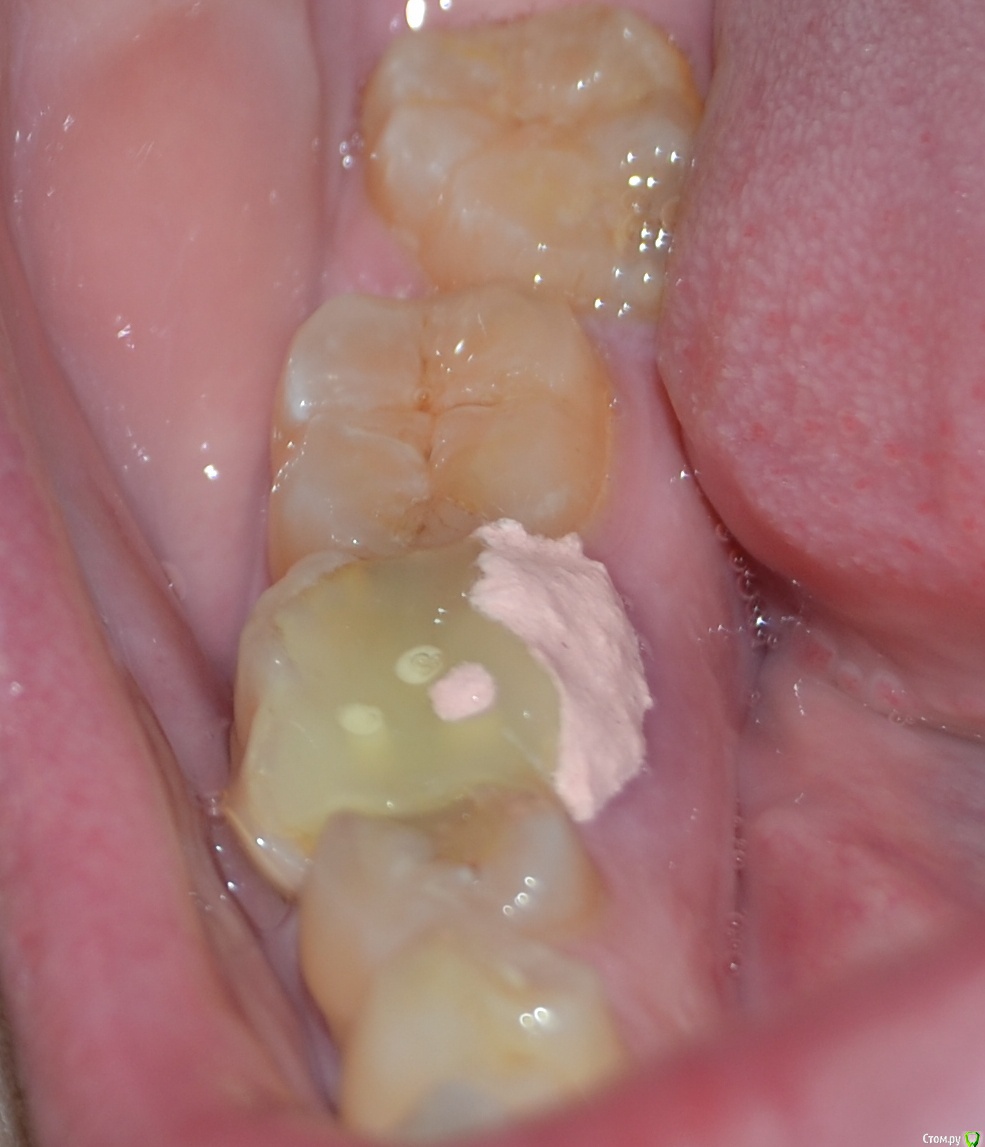

ann_bell Опубликовано 18 ноября, 2015 Поделиться Опубликовано 18 ноября, 2015 (изменено) Здравствуйте! Нужен совет. Нижняя шестерка пролечена 3 года назад, каналы запломбированы. Неделю назад откололась задняя стенка зуба. На приеме стоматолог посоветовала удалять, т.к. стенка откололась слишком глубоко. Хотя по снимку корни в порядке, никаких патологий нет.Врач сказала, что в принципе корень можно сохранить и установить коронку, но это будет дорого (перелечивание каналов 20000 + коронка с вкладкой) и конструкция будет очень ненадежной, придется постоянно подклеивать коронку. И сама врач за эту работу не возьмется, потому что вариант, мол, проигрышный изначально. Мост не хочу однозначно. Удалять и ставить имплант или попытаться сохранить коронкой? Шанс спасти все-таки есть, даже стоматолог это признала. Нужно ли его использовать?Снимок, к сожалению, остался у врача. На зуб поставили временную пломбу. Изменено 18 ноября, 2015 пользователем ann_bell Ссылка на комментарий

ann_bell Опубликовано 20 ноября, 2015 Автор Поделиться Опубликовано 20 ноября, 2015 Выкладываю снимок Ссылка на комментарий